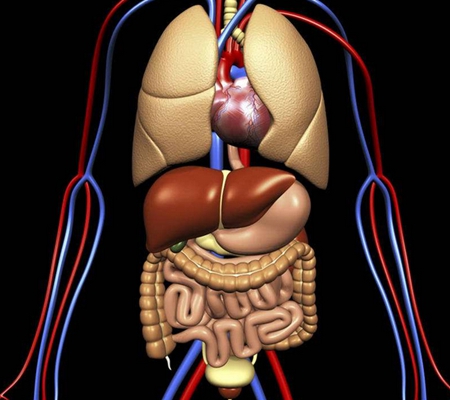

盲腸炎圖片

盲腸的位置 (50)

盲腸的位置 (6)

盲腸的位置 (7)

盲腸的位置 (8)

盲腸的位置 (9)